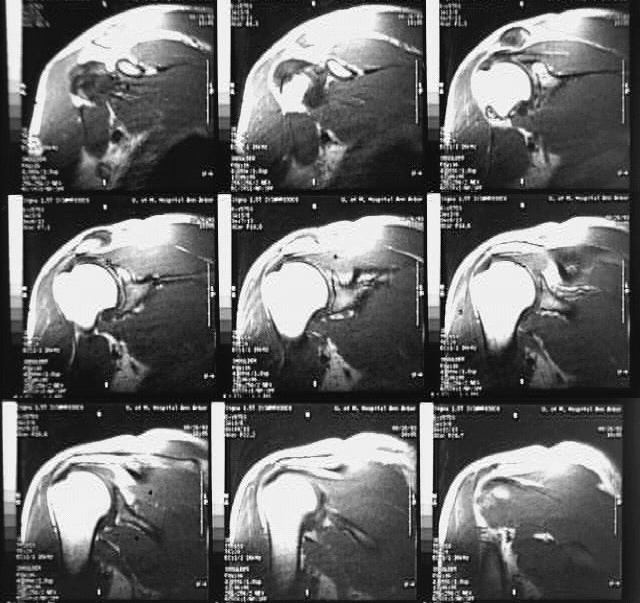

Radiology Images

Upper Limbs:Shoulder MRI: